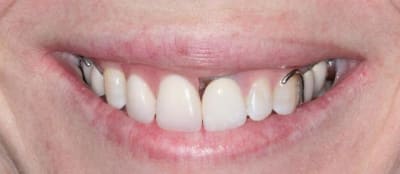

Bon ben j'ai implanté avant d'avoir refait la 21. Du coup j'ai mésialé la pose de 11 pour compenser la distalisation de 21.

Au final je n'ai pas fait de greffe osseuse... et j'ai réalisé une technique de rouleau sur 11-12 mais je reste un peu court à mon goût.

J'ai mis en place des transitoires sur 11-12-21 pour temporiser 3 mois pour voir la maturation des tissus mous.

Je réaliserai dans un second temps des piliers procera.

Je mets quelques photos de la patiente au cab et du prothèsiste d'Epinal.

La vraie difficulté a été de retrouver le milieu incisif pour déterminer la position des implants.